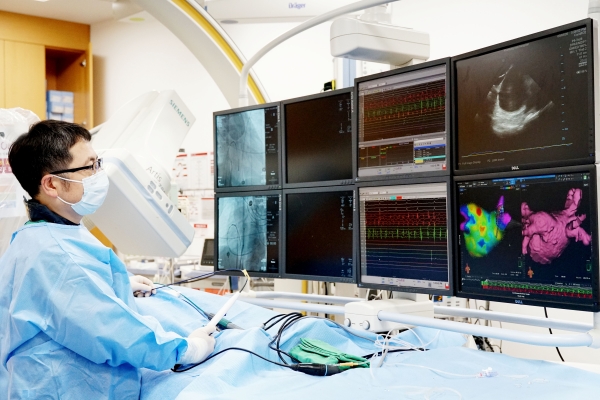

선병원재단(이사장 선두훈) 유성선병원 심장부정맥센터(센터장 최민석)가 첨단 심방세동 치료 장비 리드미아(Rhythmia Mapping System, 네비게이션 의료용 입체정위기)를 국내 최초로 정식 도입했다.

리드미아는 심방세동의 근본적 치료법인 전극도자 절제술 시행 전, 심장에서 발생하는 전기 신호를 감지해 원인 부위를 3D 고화질 영상으로 등고선 같이 보여준다. 전극도자 절제술을 시행하려면 이 매핑 과정을 반드시 거쳐야 한다.

리드미아에는 △생체전기 임피던스(신체에 미세한 전류를 통과시켜 정보를 얻는 방법)와 △마그네틱 트래킹(신체에 자장이 형성되고 전극도자 끝에 센서가 부착되어 도자 위치를 파악하는 기술) 2가지 기술이 함께 탑재돼 있어 기존의 매핑 시스템보다 해상도가 높고 해부학적 구조가 세밀하다.

특히 리드미아와 함께 사용되는 오라이온 카테터는 심장 내부의 전극 신호를 얻어 원인 부위를 찾는 데 기존 시스템보다 25배 이상 정밀하다. 정밀한 시스템 덕분에 원인 부위를 모두 보여줄 수 있고, 원인 부위에 정확히 접촉해 해당 부위를 빠르게 괴사시킬 수 있으며, 부정맥 유발 가능성이 높은 잠재적 원인 부위도 시술 할 수 있다.